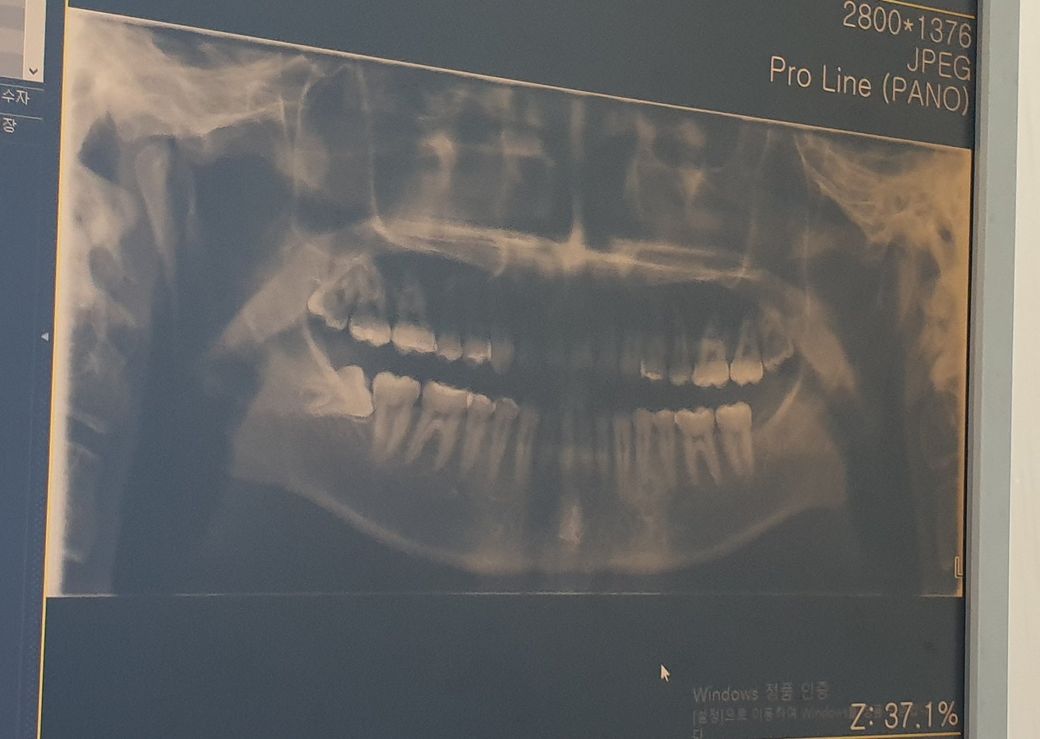

매복 사랑니 질문 빼야할까요?

최근에 오른쪽 어금니 옆에있는 사랑니 아프기 시작했습니다 이럴때 병원을 가야할지 아님 참고 더아프면은 그때 가야할지 고민이됩니다 아래에 최근에 찍은 치아 엑스레이 올려놨는데 어떻게 해야하나요..

현재 파노라마 사진으로 보았을때는 우측 아래 사랑니가 부분 매복되어 있고 옆으로 나 있습니다. 보시면 알겠지만 사랑니와 어금니 사이에 공간이 있어 음식물이 자주 저류될 수 있어 충치 등이 많이 발생할 것으로 보여집니다.

지금 사진으로는 정확히 알 수 없으나 큰 충치나 앞쪽 어금니에 미친 영향이 없어 보이나 지속적으로 방치시 사랑니도 썩고 앞쪽 어금니도 썩을 수 있습니다.

시일내로 방문하셔서 빼시는게 좋을 듯 해보입니다. 이미 잇몸 위로 올라온 것 같은데 사랑니와 제2대구치 사이에 음식물이 낄수 있어 보이고 그 사이는 관리가 어려워 두 치아 모두 충치가 생길 확률이 높습니다. 또한 사랑니가 제2대구치를 밀고 있는 것처럼 보이는데 제2대구치의 뒤쪽면 뿌리와 치조골에도 안 좋은 영향을 미칠 수 있습니다.

사랑니의 뿌리사이에 신경이 지나가는 것 처럼 보이는데 영상이 흐릿해서 정확하지 않으니 치과에 내원하셔서 발치가능여부를 확인해보시고 치과대학병원에 방문하시는 것도 좋을 듯 해보입니다.

오른쪽 아래의 매복된 사랑니의 경우 잇몸밖으로나와있기 때문에 안에 이물질이 잘 들어가게 되어 앞에 있는 치아에 충치를 발생시키거나 잇몸에 염증을 쉽게 유발할수 있습니다.

오른쪽 아래 사랑니는 옆으로 누워있는 수평매복지치를 질문하신 것으로 생각됩니다. 그냥 두면 바로 앞 어금니가 손상되니 빼십시요.